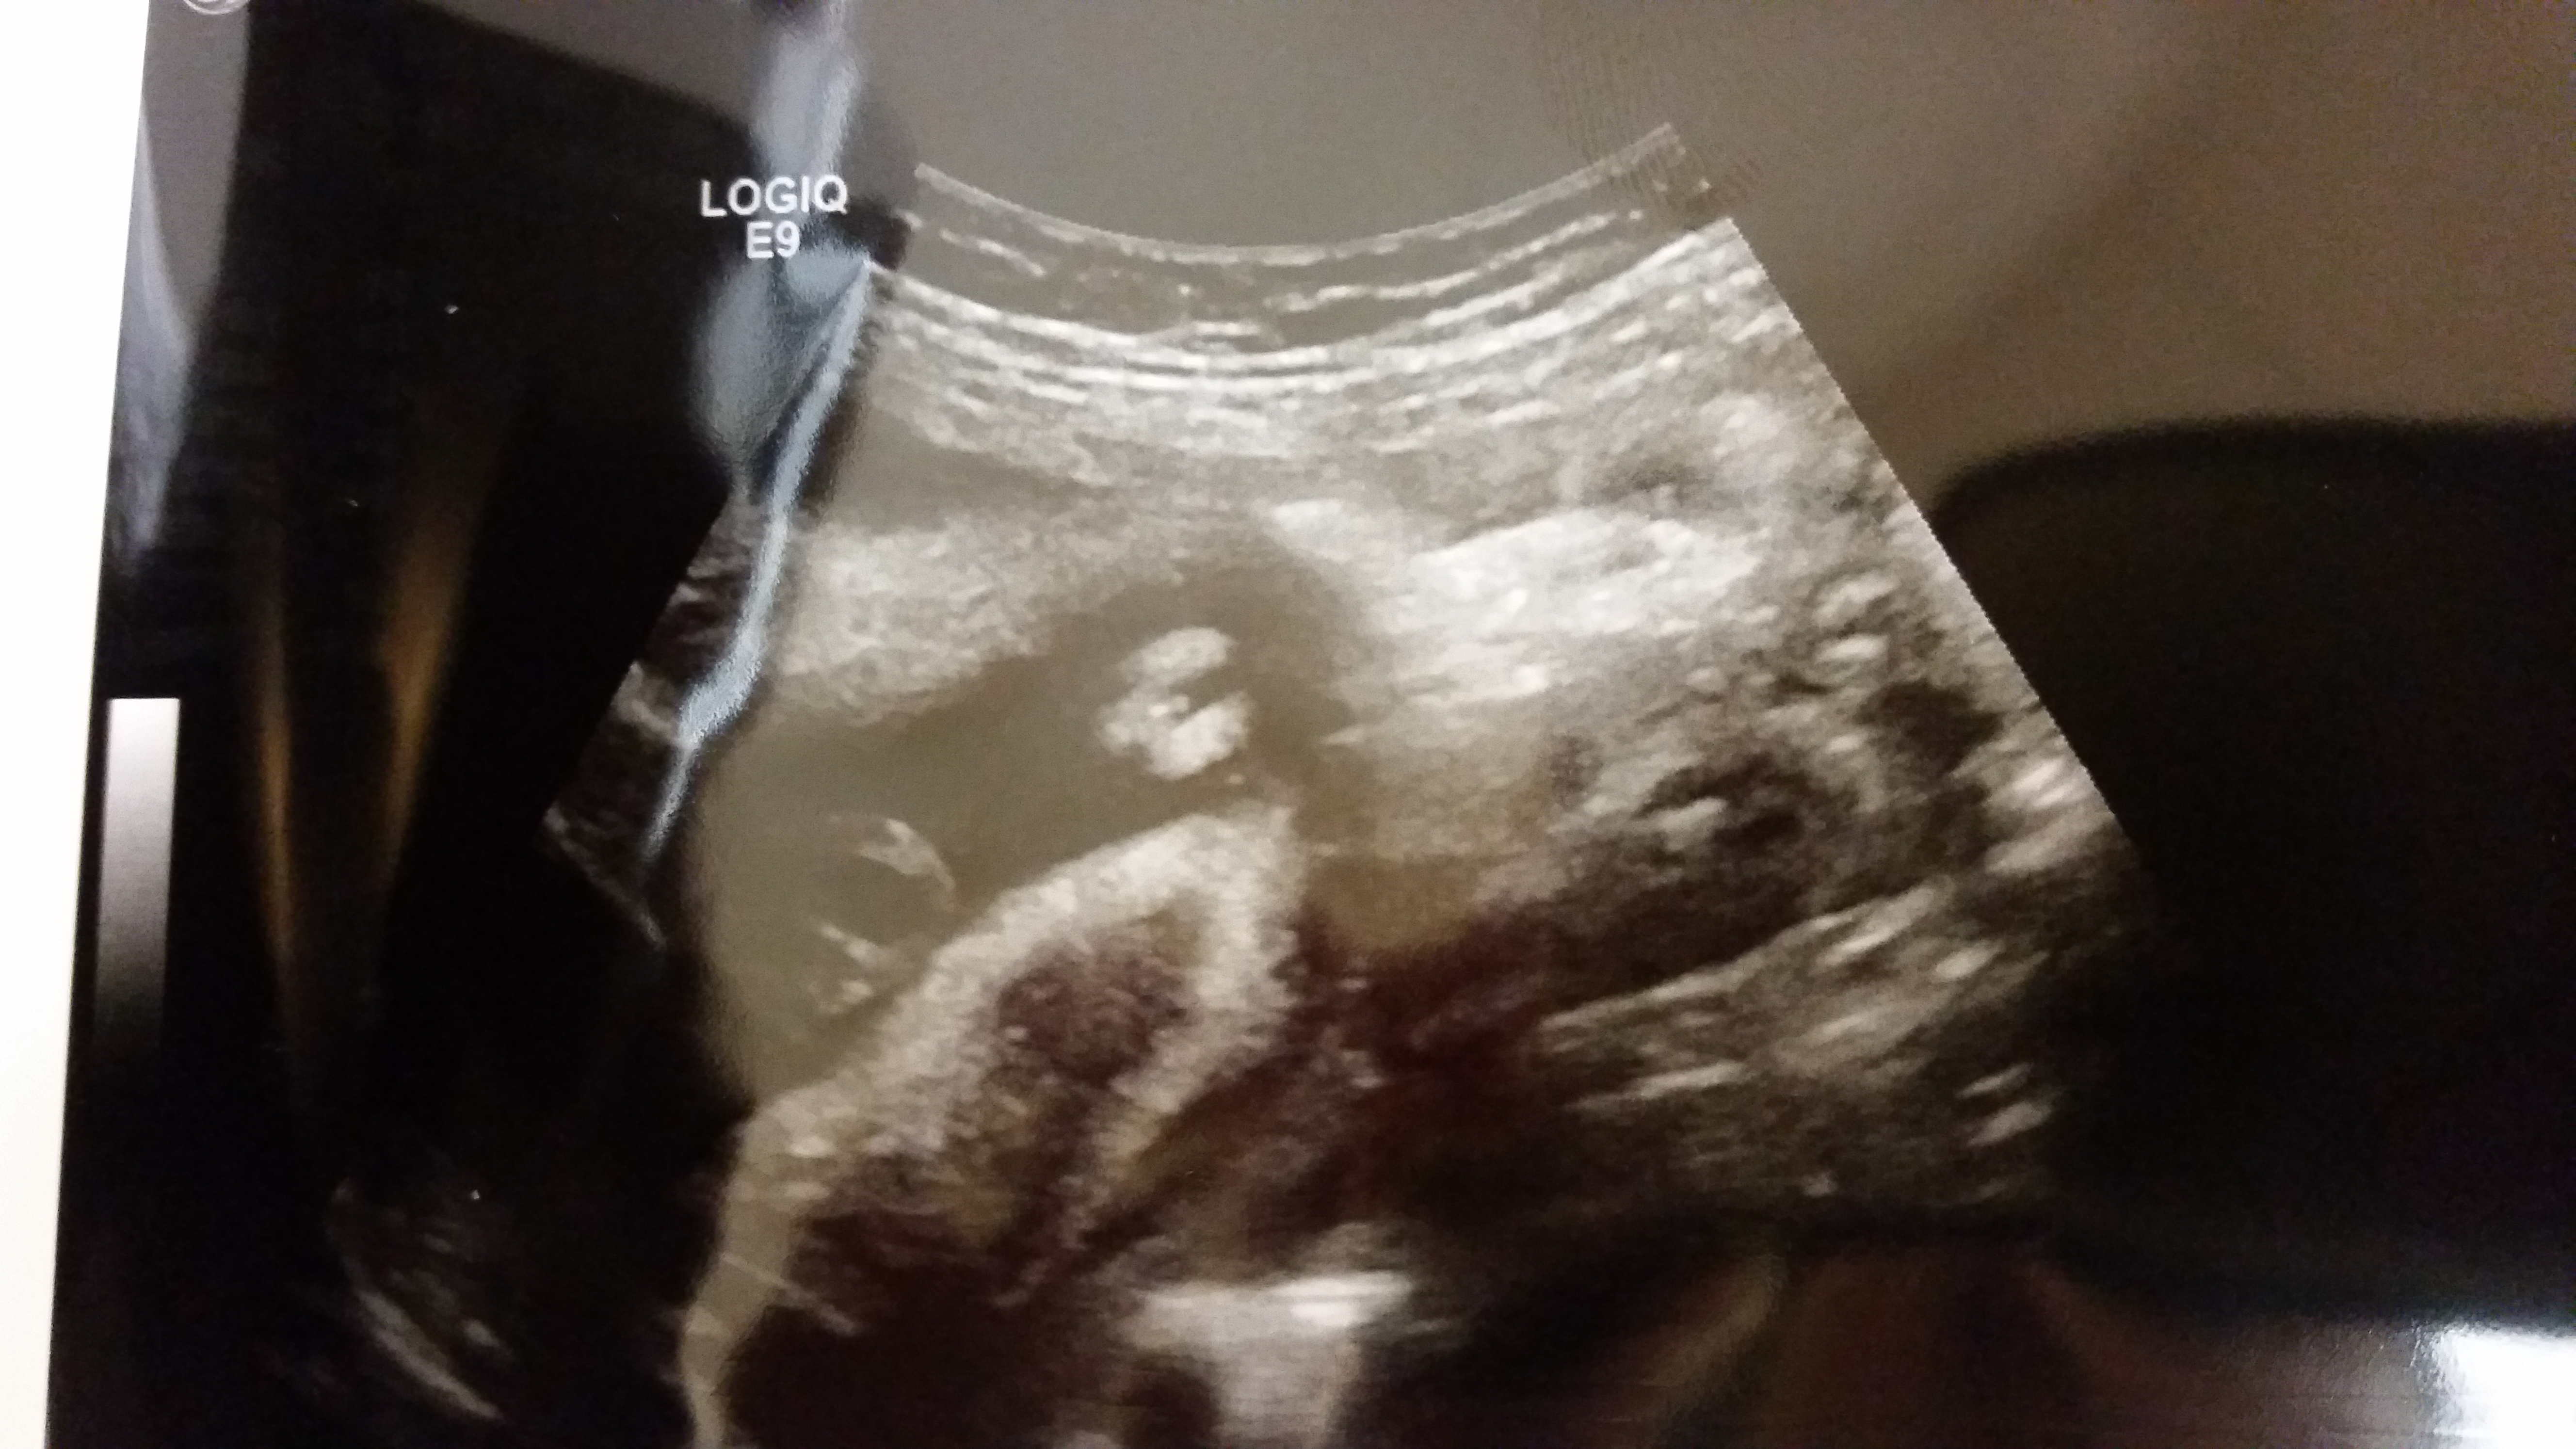

I had posted an ultrasound photo from baby's 20 week anatomy scan and I had mixed guesses of boy and girl. I just went in for a follow-up ultrasound today and the sonographer is pretty sure she's a girl but not 100% since the center is protruding quite a bit for almost 25 weeks. Would like your opinions!

Attachment 21130